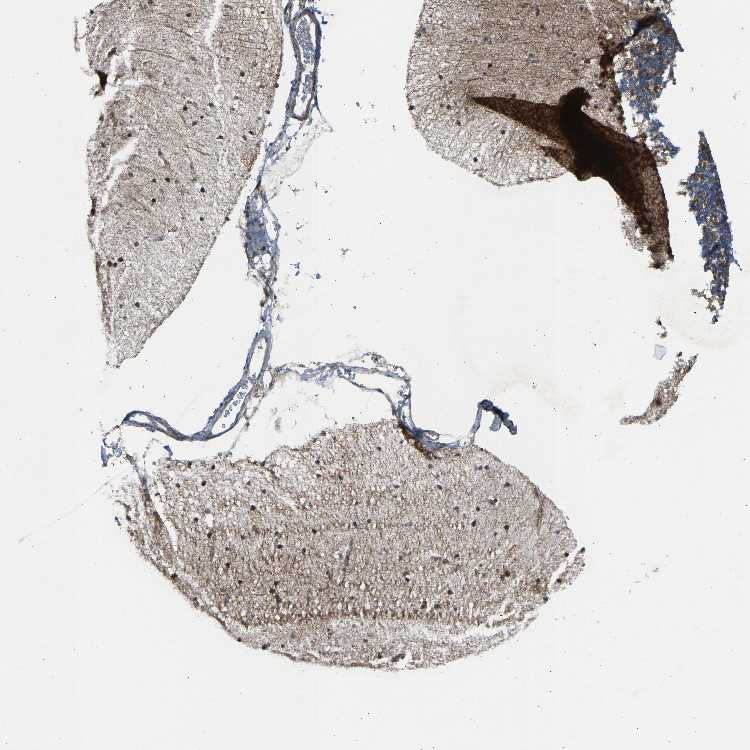

CEREBELLUM - Antibody stainingi

Antibody staining in the annotated cell types in the current human tissue is reported as not detected, low, medium, or high, based on conventional immunohistochemistry profiling in selected tissues. This score is based on the combination of the staining intensity and fraction of stained cells.

Each image is clickable and will lead to virtual microscopy that enables deeper exploration of all samples and also displays staining intensity scores, fraction scores and subcellular localization as well as patient and tissue information for each sample.

Antibody HPA020080Antibody HPA020299

Purkinje cells MediumHigh

Cells in granular layer LowMedium

Cells in molecular layer LowMedium